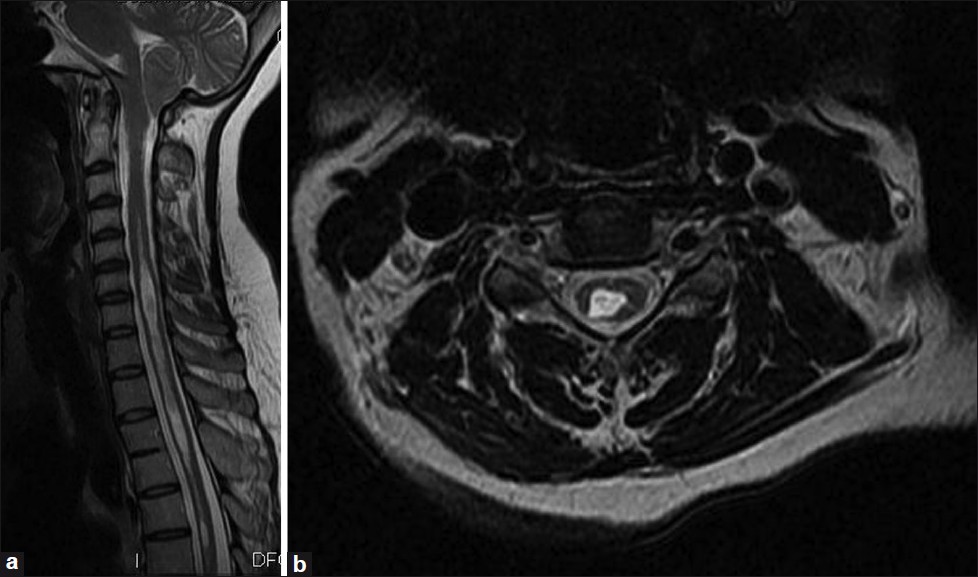

Magnetresonanz-Bildgebung (MRI)

Computerisierte Axialtomographie (CAT) -Scan